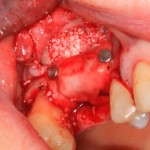

Рисунок 43, 44, 45. Установка имплантов одномоментно с операцией синуслифтинга: слева – этап синуслифтинга, в центре – подготовка лунки под имплантат (виден спейсер и слизистая оболочка гайморовой пазухи), справа – установленный имплант

Оптимальное расстояние от дна гайморовой пазухи до верхней точки альвеолярного гребня верхней челюсти, при котором возможна стабилизация импланта длиной 10-11 мм – не менее 3-4 мм. Однако, в некоторых случаях имплантат длиной 11 мм удается стабилизировать в меньшем объеме костной ткани (рис 46, 47, 48):

Рисунок 46, 47, 48. Стабилизация импланта при толщине костной ткани менее 3 мм: слева – установка импланта после синуслифтинга, в центре – заполнение субантрального пространства спейсером, справа – рентгенологический контроль.